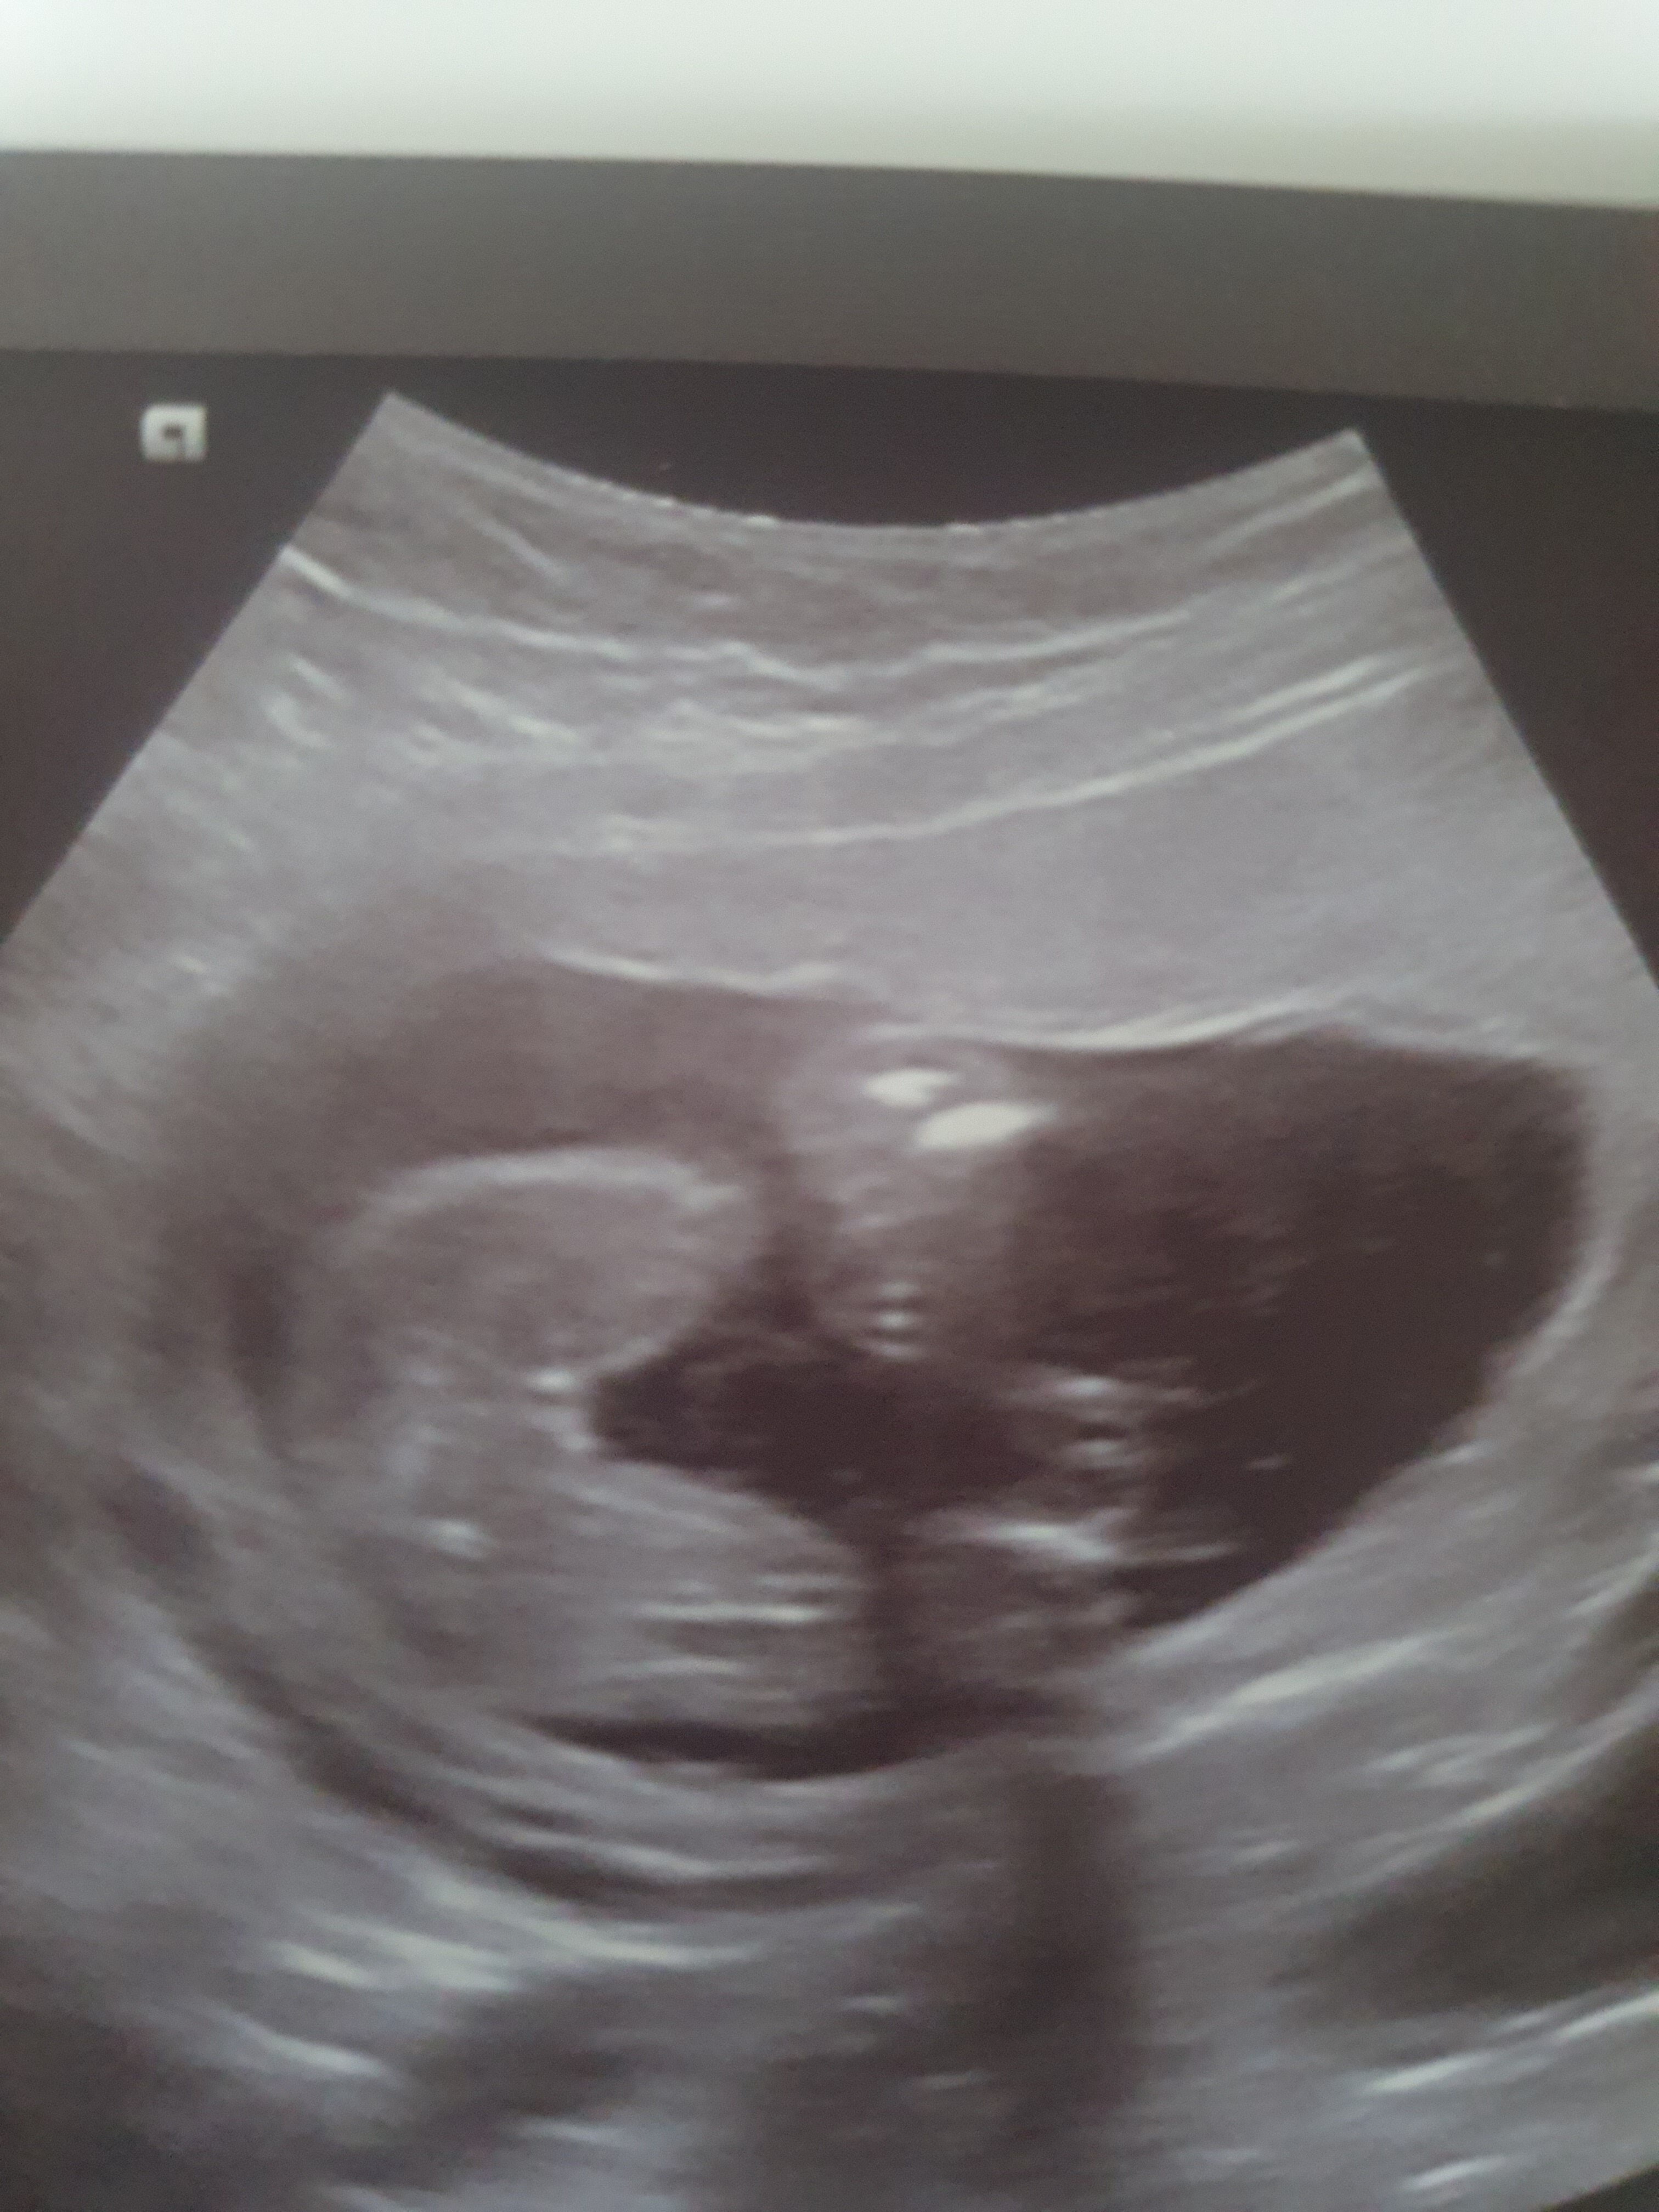

Hej dziewczyny co powiecie. Na to usg . Zaczne od tego ze to moja druga ciaza (przy corce pierwszej sie lekarz nie pomylil do samego konca a bylo to 8 lat temu) na nrz ten sam lekarz i w 14 tygodniu powiedzial mi sam ze bede miala syna. Po czym dwa tygodnie pozniej czyli do wczoraj pojechalam na usg prywatne 3d/4d i tam pani dr stwierdziła dziewczynke . Ja juz sama nie wiem zrekniecie bo ciagle nie dowierzam i ludze se na ta pierwsza wresje ze jednak bedzie synek tym razem..

Myslicie ze w tyg 15+6 na badaniu 3d/ 4d mogla sie pomylic sa jakies szanse ze jeszcze z tego bedzie chlopiec ? 😁 Dodam że gdy zapytalam czy to pewne odpowiedź brzmiala,, to zalezy na ile pani mi ufa,, no o w opisie nie opisala nic ze dziecko jest o pluci zenskiej 🤔